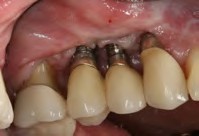

Fig 8. Poor implant positioning illustrates that a surgical template either was not used or ignored.

Figure 8

Fig 9. Late (ie, post-loading) bone loss resulted, necessitating removal of implants, replacement, use of other sites/implants, and/or submerging, in addition to the use of tissue grafts.

Figure 9